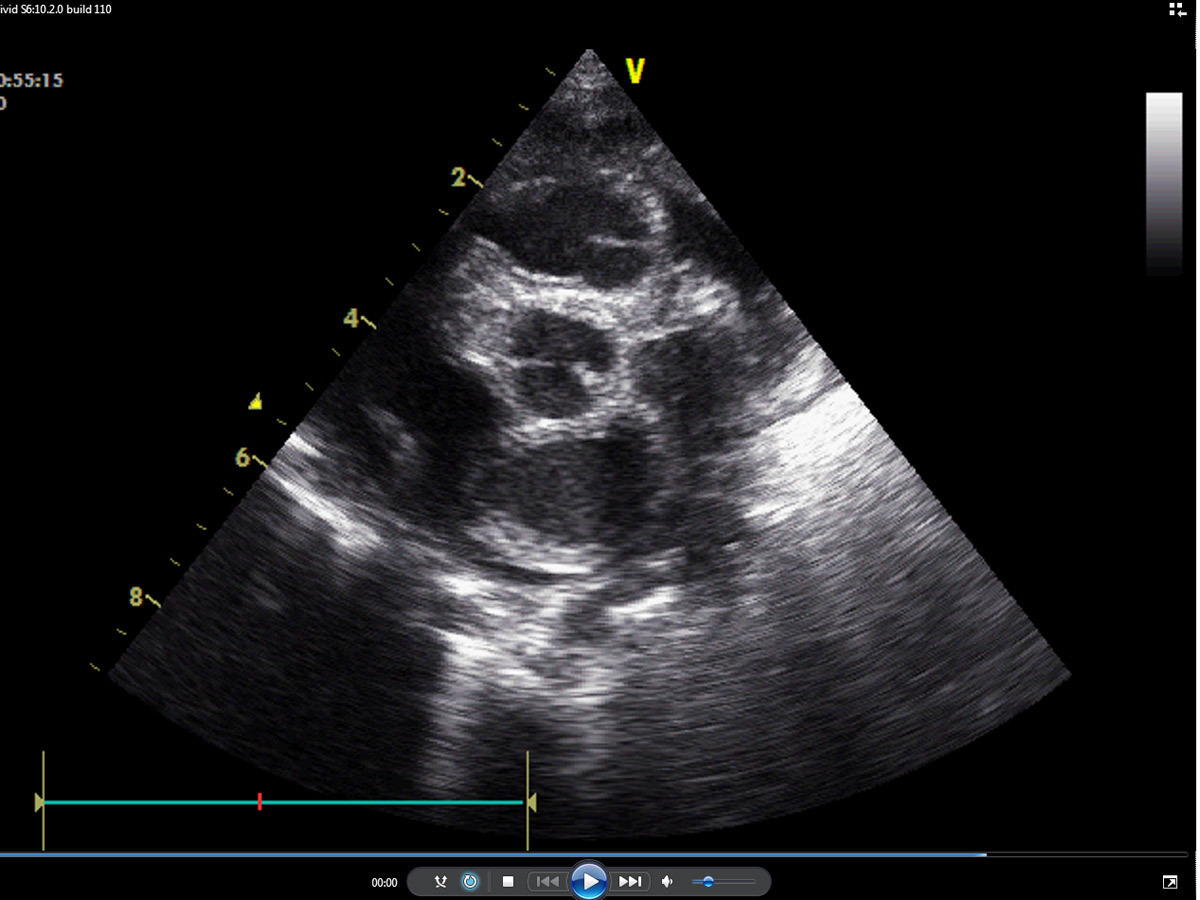

Certaines cardiopathies ne soufflent pas, d’autres soufflent plus tardivement (communication interventriculaire [CIV] par exemple)